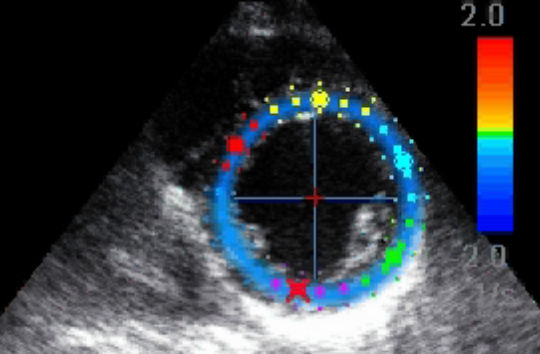

Συγγραφείς: M. N. Alekhin, S. I. Ivanov, N. F. Radova, М. Н. Алёхин, С. И. Иванов, Н. Ф. Радова

Πηγή: Siberian Journal of Clinical and Experimental Medicine; Том 38, № 3 (2023); 75-85 ; Сибирский журнал клинической и экспериментальной медицины; Том 38, № 3 (2023); 75-85 ; 2713-265X ; 2713-2927

Θεματικοί όροι: стресс-эхокардиография, pressure-strain loop, coronary artery disease, stress echocardiography, кривая давление-деформация, ишемическая болезнь сердца

Περιγραφή αρχείου: application/pdf

Relation: https://www.sibjcem.ru/jour/article/view/1945/861; Cameli M., Mandoli G.E., Sciaccaluga C., Mondillo S. More than 10 years of speckle tracking echocardiography: Still a novel technique or a definite tool for clinical practice? Echocardiography. 2019;36(5):958–970. DOI:10.1111/echo.14339.; Choi J.O., Cho S.W., Song Y.B., Cho S.J., Song B.G., Lee S.C. et al. Longitudinal 2D strain at rest predicts the presence of left main and three vessel coronary artery disease in patients without regional wall motion abnormality. Eur. J. Echocardiogr. 2009;10(5):695–701. DOI:10.1093/ejechocard/jep041.; Smiseth O.A., Torp H., Opdahl A., Haugaa K.H., Urheim S. Myocardial strain imaging: how useful is it in clinical decision making? Eur. Heart J. 2016;37(15):1196–1207. DOI:10.1093/eurheartj/ehv529.; Yingchoncharoen T., Agarwal S., Popović Z.B., Marwick T.H. Normal ranges of left ventricular strain: a meta-analysis. J. Am. Soc. Echocardiogr. 2013;26(2):185–191. DOI:10.1016/j.echo.2012.10.008.; Russell K., Eriksen M., Aaberge L., Wilhelmsen N., Skulstad H., Remme E.W. et al. A novel clinical method for quantification of regional left ventricular pressure-strain loop area: a non-invasive index of myocardial work. Eu.r Heart J. 2012;33(6):724–733. DOI:10.1093/eurheartj/ehs016.; Ilardi F., D’Andrea A., D’Ascenzi F., Bandera F., Benfari G., Esposito R. et al. Myocardial work by echocardiography: principles and applications in clinical practice. J. Clin. Med. 2021;10(19):4521. DOI:10.3390/jcm10194521.; Boe E., Russell K., Eek C., Eriksen M., Remme E.W., Smiseth O.A. et al. Non-invasive myocardial work index identifies acute coronary occlusion in patients with non-ST-segment elevation-acute coronary syndrome. Eur. Heart J. Cardiovasc.Imaging. 2015;16(11):1247–1255. DOI:10.1093/ehjci/jev078.; Butcher S.C., Lustosa R.P., Abou R., Marsan N.A., Bax J.J., Delgado V. Prognostic implications of left ventricular myocardial work index in patients with ST-segment elevation myocardial infarction and reduced left ventricular ejection fraction. Eur. Heart J. Cardiovasc. Imaging. 2022;23(5):699–707. DOI:10.1093/ehjci/jeab096.; Edwards N.F.A., Scalia G.M., Shiino K., Sabapathy S., Anderson B., Chamberlain R. et al. Global myocardial work is superior to global longitudinal strain to predict significant coronary artery disease in patients with normal left ventricular function and wall motion. J. Am. Soc. Echocardiogr. 2019;32(8):947–957. DOI:10.1016/j.echo.2019.02.014.; Sabatino J., De Rosa S., Leo I., Strangio A., Spaccarotella C., Polimeni A. et al. Prediction of significant coronary artery disease through advanced echocardiography: Role of non-invasive myocardial work. Front. Cardiovasc. Med. 2021;8:719603. DOI:10.3389/fcvm.2021.719603.; Edwards N.F.A., Scalia G.M., Sabapathy S., Anderson B., Chamberlain R., Khandheria B.K. et al. Resting global myocardial work can improve interpretation of exercise stress echocardiography. Int. J. Cardiovasc. Imaging. 2021;37(8):2409–2417. DOI:10.1007/s10554-021-02216-0.; Borrie A., Goggin C., Ershad S., Robinson W., Sasse A. Noninvasive myocardial work index: Characterizing the normal and ischemic response to exercise. J. Am. Soc. Echocardiogr. 2020;33(10):1191–1200. DOI:10.1016/j.echo.2020.05.003.; Sabatino J., De Rosa S., Leo I., Spaccarotella C., Mongiardo A., Polimeni A. et al. Non-invasive myocardial work is reduced during transient acute coronary occlusion. PLoS One. 2020;15(12):e0244397. DOI:10.1371/journal.pone.0244397.; Patel M.R., Calhoon J.H., Dehmer G.J., Grantham J.A., Maddox T.M., Maron D.J. et al. ACC/AATS/AHA/ASE/ASNC/SCAI/SCCT/STS 2017 Appropriate use criteria for coronary revascularization in patients with stable ischemic heart disease: A Report of the American College of Cardiology Appropriate Use Criteria Task Force, American Association for Thoracic Surgery, American Heart Association, American Society of Echocardiography, American Society of Nuclear Cardiology, Society for Cardiovascular Angiography and Interventions, Society of Cardiovascular Computed Tomography, and Society of Thoracic Surgeons. J. Am. Coll. Cardiol. 2017;69(17):2212–2241. DOI:10.1016/j.jacc.2017.02.001.; Lang R.M., Badano L.P., Mor-Avi V., Afilalo J., Armstrong A., Ernande L. et al. Recommendations for cardiac chamber quantification by echocardiography in adults: an update from the American Society of Echocardiography and the European Association of Cardiovascular Imaging. J. Am. Soc. Echocardiogr. 2015;28(1):1–39.e14. DOI:10.1016/j.echo.2014.10.003.; Pellikka P.A., Arruda-Olson A., Chaudhry F.A., Chen M.H., Marshall J.E., Porter T.R. et al. Guidelines for performance, interpretation, and application of stress echocardiography in ischemic heart disease: From the American Society of Echocardiography. J. Am. Soc. Echocardiogr. 2020;33(1):1–41.e8. DOI:10.1016/j.echo.2019.07.001.; Mansour M.J., Al Jaroudi W., Mansour L., Nehme A., Hamoui O., Ayoub W. et al. Value of myocardial work for assessment of myocardial adaptation to increased afterload in patients with high blood pressure at peak exercise. Int. J. Cardiovasc. Imaging. 2020;36(9):1647–1656. DOI:10.1007/s10554-020-01867-9.; Edwards N.F.A., Scalia G.M., Putrino A., Appadurai V., Sabapathy S., Anderson B. et al. Myocardial work and left ventricular contractile reserve during stress echocardiography: An angiographic validation. Echocardiography. 2021;38(10):1711–1721. DOI:10.1111/echo.15194.; Zhang J., Liu Y., Deng Y., Zhu Y., Sun R., Lu S. Non-invasive global and regional myocardial work predicts high-risk stable coronary artery disease patients with normal segmental wall motion and left ventricular function. Front. Cardiovasc. Med. 2021;8:711547. DOI:10.3389/fcvm.2021.711547.; https://www.sibjcem.ru/jour/article/view/1945